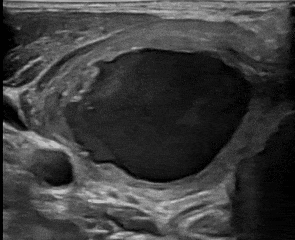

超声检查后发现徐先生颈部“鼓包”为甲状腺结节出血后改变。考虑到患者的年龄及明确拒绝手术的强烈要求,临床医生建议徐先生选择超声介入微创治疗。

超声介入亚专科王晓明副主任医师对患者再次进行超声评估,确认患者颈部“鼓包”大小4*3*4cm,几乎为囊性,边缘伴有少许实性结构,适合超声引导下抽液硬化治疗,但谨慎起见,术前有必要对边缘实性结构进行细针穿刺细胞学检查,确认良性后方可行抽液硬化治疗。

▲超声引导下抽液硬化治疗

细胞学病理结果证实为良性后,超声介入团队王晓明副主任医师与朱帆主治医师通力合作,在超声实时引导下用一根1mm左右的细针对患者颈部“鼓包”进行精准穿刺,抽出暗红色液体30ml,部分送检行脱落细胞学检查。后用生理盐水对囊腔进行多次冲洗置换,直至冲洗液达清亮后抽出,注入聚桂醇(新型化学硬化剂)反复冲洗多次,静置5分钟后抽出囊液,此时囊液显示为酒红色,证明硬化效果比较好,最后再次注入聚桂醇后留置。